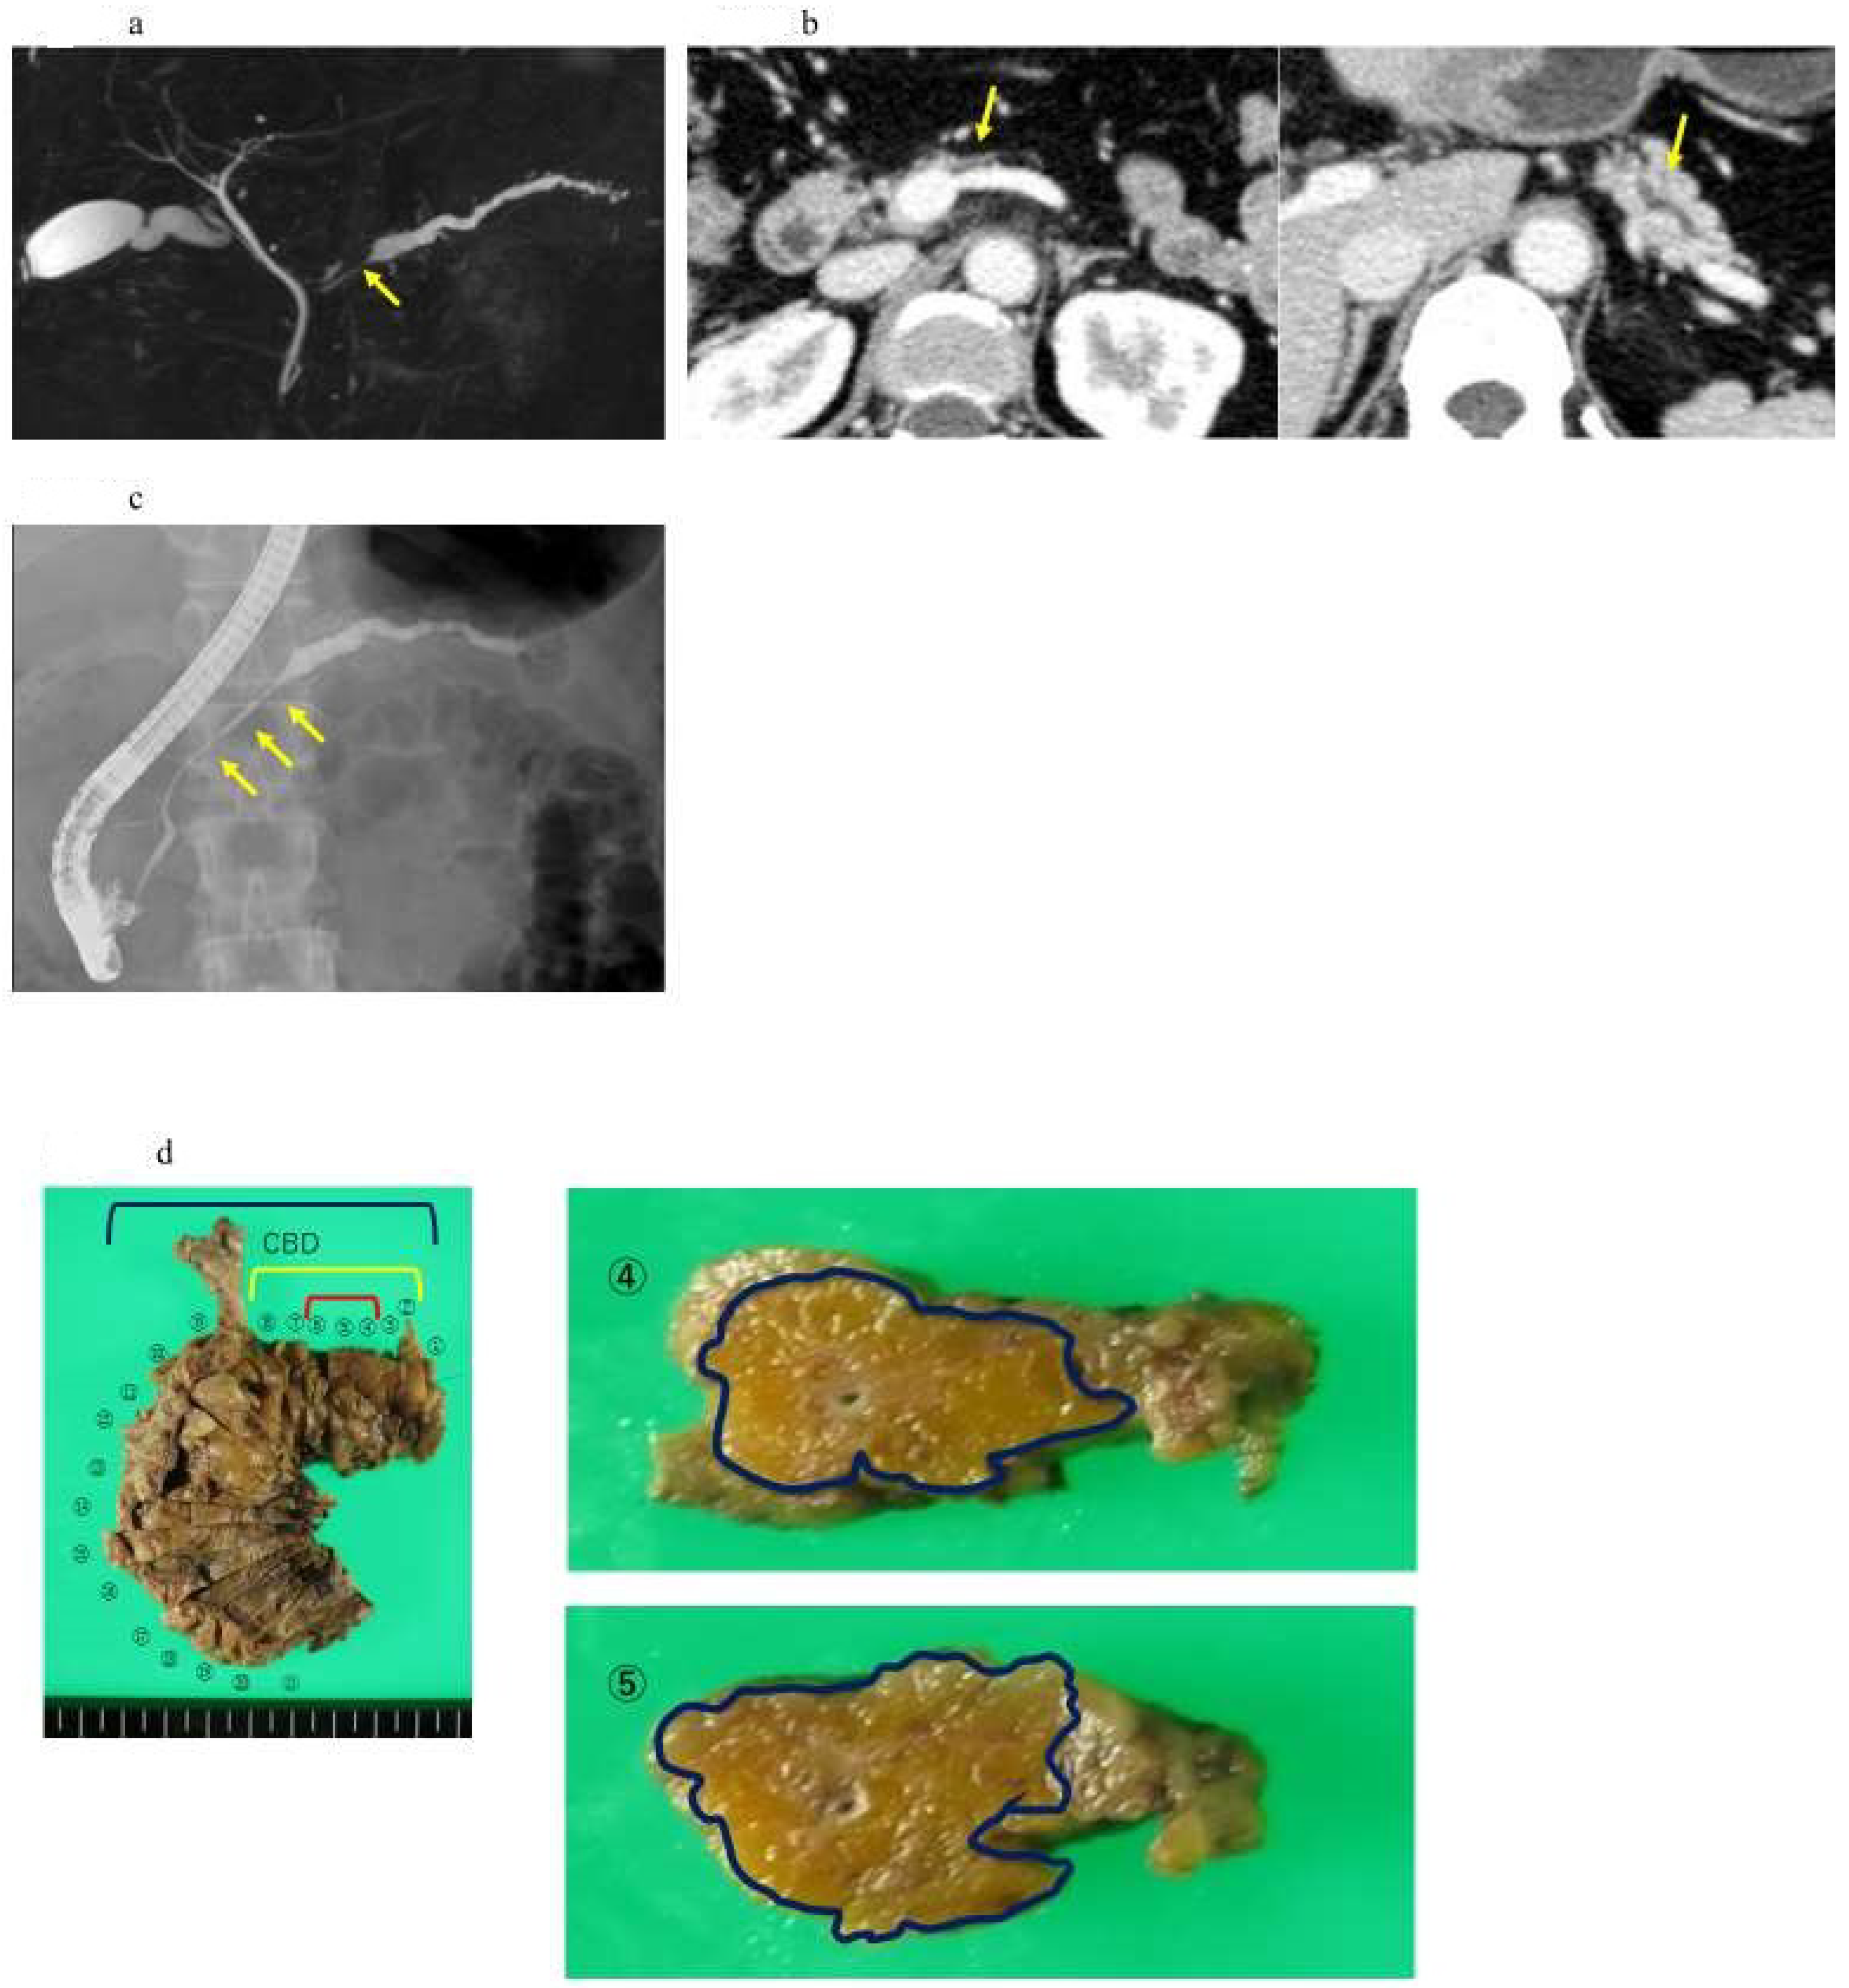

Figure 4.

A case of intraepithelial carcinoma of the pancreas, early-stage PDAC, in which no pancreatic tumor was found by CT or MRI imaging, but severe lipidosis of the pancreatic body was observed, leading to the diagnosis of a pancreatic tumor by pancreatic fluid cytology. (a) Magnetic resonance cholangiopancreatography showing stenosis of the MPD (yellow arrow) and dilation of the MPD and branch ducts in the caudal part. (b) Enhanced CT showing localized atrophic change (yellow arrow) in the pancreatic body and dilation of the MPD in the caudal part. (c) Endoscopic retrograde cholangiography demonstrating stenosis of the MPD in the pancreatic body (yellow arrow) and detailed in the caudal part. (d) In the resected specimens, severe stenosis of the main pancreatic duct was observed in the resected sections 2–8 (yellow frame), and, in particular, severe steatosis was observed in the resected sections 2–11 (out of the blue frames, 4 and 4). Additionally, 5 shows the resected section. High-grade PanIN was detected in the 4, 5, and 6 resected sections of the pancreatic body (red frame). (e) Pathological findings indicated the low papillary proliferation of the pancreatic duct epithelium in the lumen of the main pancreatic duct of pancreatic bodies 4, 5, and 6 and pancreatic lobules associated with chronic pancreatitis in the surrounding pancreatic tissue. Disappearance, fatification, and remaining islets of Langerhans were observed (HE × 40). The pancreatic ductal epithelium exhibited nucleomegaly, a mild chromatin increase, and some clear nucleoli, and high-grade PanIN was detected (HE × 100).